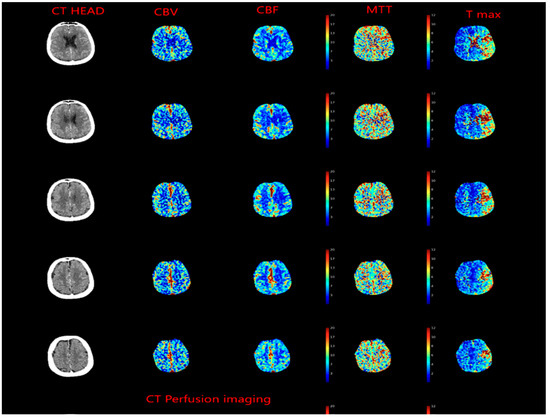

2.5. Evolution of the Concept of the Tissue Window and Late Window Trials